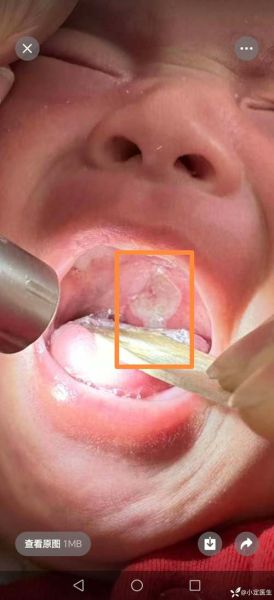

不少家长把四个月宝宝口腔溃疡图与鹅口疮混淆,结果用错药。快速区分要点:

- 颜色:溃疡中心呈乳黄或灰白色,边缘红;鹅口疮为均匀奶块样白斑。

- 形状:溃疡边缘不规则,略凹陷;鹅口疮表面凸起,擦不掉。

- 痛感:溃疡一碰就哭;鹅口疮早期往往无痛。